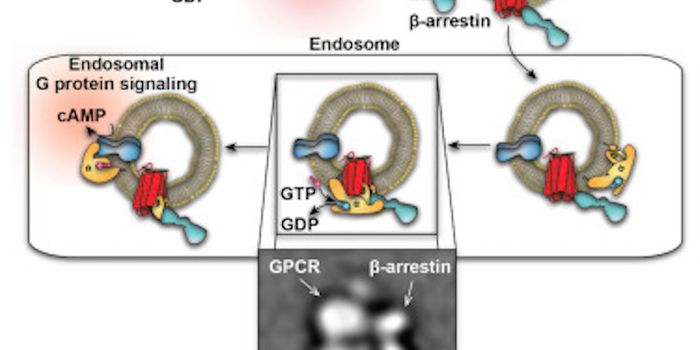

AUG 11, 2016Cell & Molecular BiologyIn new research published in the journal Angewandte Chemie, scientists applied a high throughput methodology to study th ...